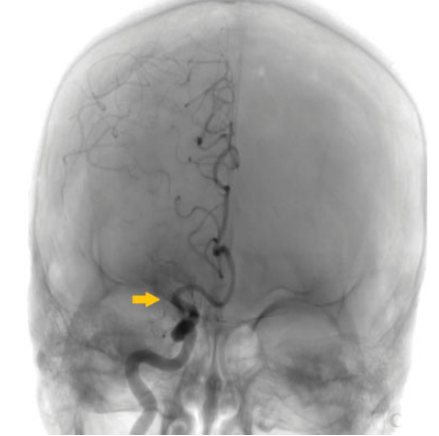

De nuestra serie de casos (n ¼ 228), solo se encontraron complicaciones en el 16,6%: hemorragias subaracnoideas secundarias a perforación (n ¼ 2) (►Fig. 1), hemorragia gangliobasal (n ¼ 1) (►Fig. 2), vasoespasmo (n ¼ 1), disección (n ¼ 1) (►Fig. 3), embolias (n ¼ 31) y pseudoaneurismas (n ¼ 2) (►Fig. 4) en el sitio de la punción. Cuando se detectó oclusión intracraneal (►Fig. 5), tras la trombectomía, dentro del grupo de las embolias, solo el 16,1% se presentaron hacia nuevo territorio vascular (arteria cerebral anterior) (►Fig. 6) o embolias distales. Debido al bajo número de complicaciones, se realizó un análisis mediante Fisher que da un resultado no significativo (►Tabla 3). Las hemorragias fueron subaracnoideas detectadas durante las trombectomías como la extravasación activa del contraste y corroborada mediante tomografía computada (TC) al finalizar el procedimiento. El vasoespasmo que se presentó fue moderado en arteria cerebral media izquierda que cedió tras la infusión intra-arterial de 0,2 mg nimodipino.

La flecha señala el sitio de la oclusión en el origen de la arteria cerebral media (ACM) derecha en arteriografía convencional.

Arteriografía convencional. La flecha amarilla señala embolia postrombectomía en la ACM por fragmentación hacia el segmento A2 de la arteria cerebral anterior (ACA) ipsilateral, con restauración parcial del flujo a nivel de M1 del mismo lado.

Del total de embolias el mayor porcentaje se encontró en el grupo de stent-retriever, (►Tabla 4), sin embargo, no se encontró relación estadísticamente significativa entre la técnica y la aparición de embolia distal (Chi-cuadrado: X2 ¼ , 862 p ¼ ,353).